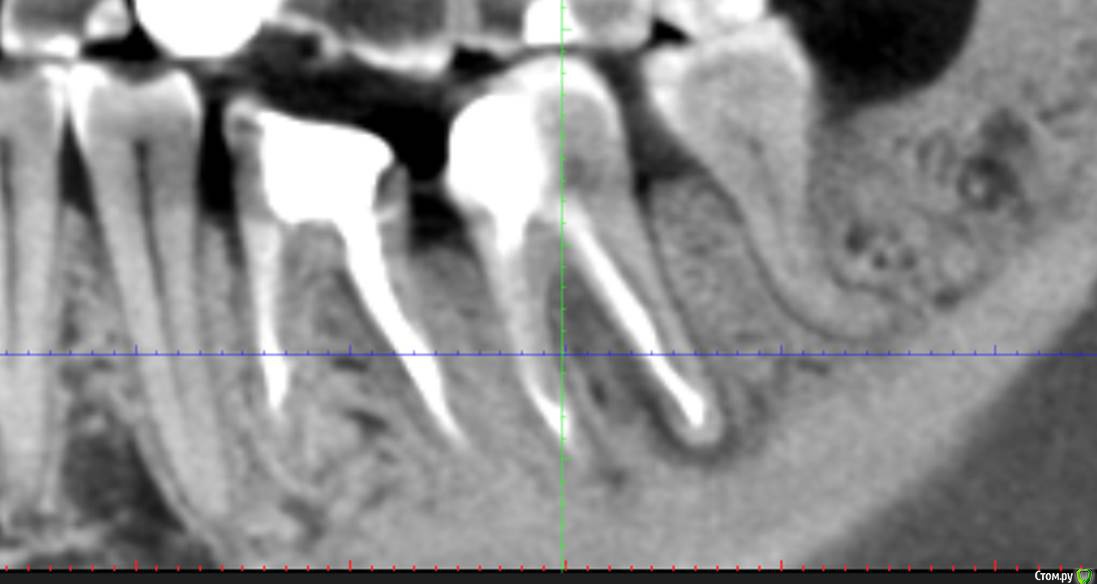

Сева северный Опубликовано 26 апреля, 2016 Автор Поделиться Опубликовано 26 апреля, 2016 Пошаманили .... через 3.5 месяца. Ссылка на комментарий

Сева северный Опубликовано 27 апреля, 2016 Автор Поделиться Опубликовано 27 апреля, 2016 (изменено) Это надо в Вк запостить, для удаляторов)Да там такого много. Вопрос удаления. конечно рассматривался... Но для имплантации, потеря зоны костной перегородки в зоне бифуркации, достаточно критична. Поэтому.. приняли решение эндосанации . (повыращивать кость), а в случае успеха обойтись без нее. Как показывает практика, большие очаги, особенно если не ступала ((((нога стоматолога , с гипохлоридом, быстро... схлопываются. Изменено 27 апреля, 2016 пользователем Сева северный 2 Ссылка на комментарий

DmitrySH Опубликовано 27 апреля, 2016 Поделиться Опубликовано 27 апреля, 2016 Точно, при "девственных каналах" периодонтиты лечатся отлично. 2 Ссылка на комментарий